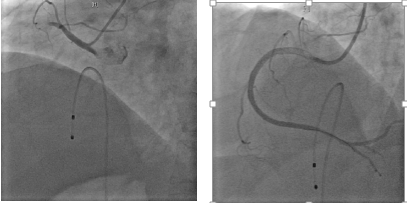

急性心肌梗死合并III度房室传导阻滞,病情极其危重,需紧急行冠脉造影及介入治疗,开通闭塞血管。但黄老今日独自一人出门,儿女均不在身边,无人替黄老签署知情同意书。在此危急情况下,北京清华长庚医院立刻启动绿色通道,在行政总值班见证下,征求黄老同意后,立即于心脏内科导管室行急诊冠脉造影。,冠脉造影显示:RCA近段100%闭塞,考虑右冠状动脉闭塞引发急性心肌梗死及心动过缓,术中即刻开通闭塞血管,此时距黄老踏入我院急诊仅30分钟,距黄老发病仅70分钟。

图3:造影提示右冠状动脉完全闭塞(左);术中开通右冠脉并植入支架后血流恢复正常(右)